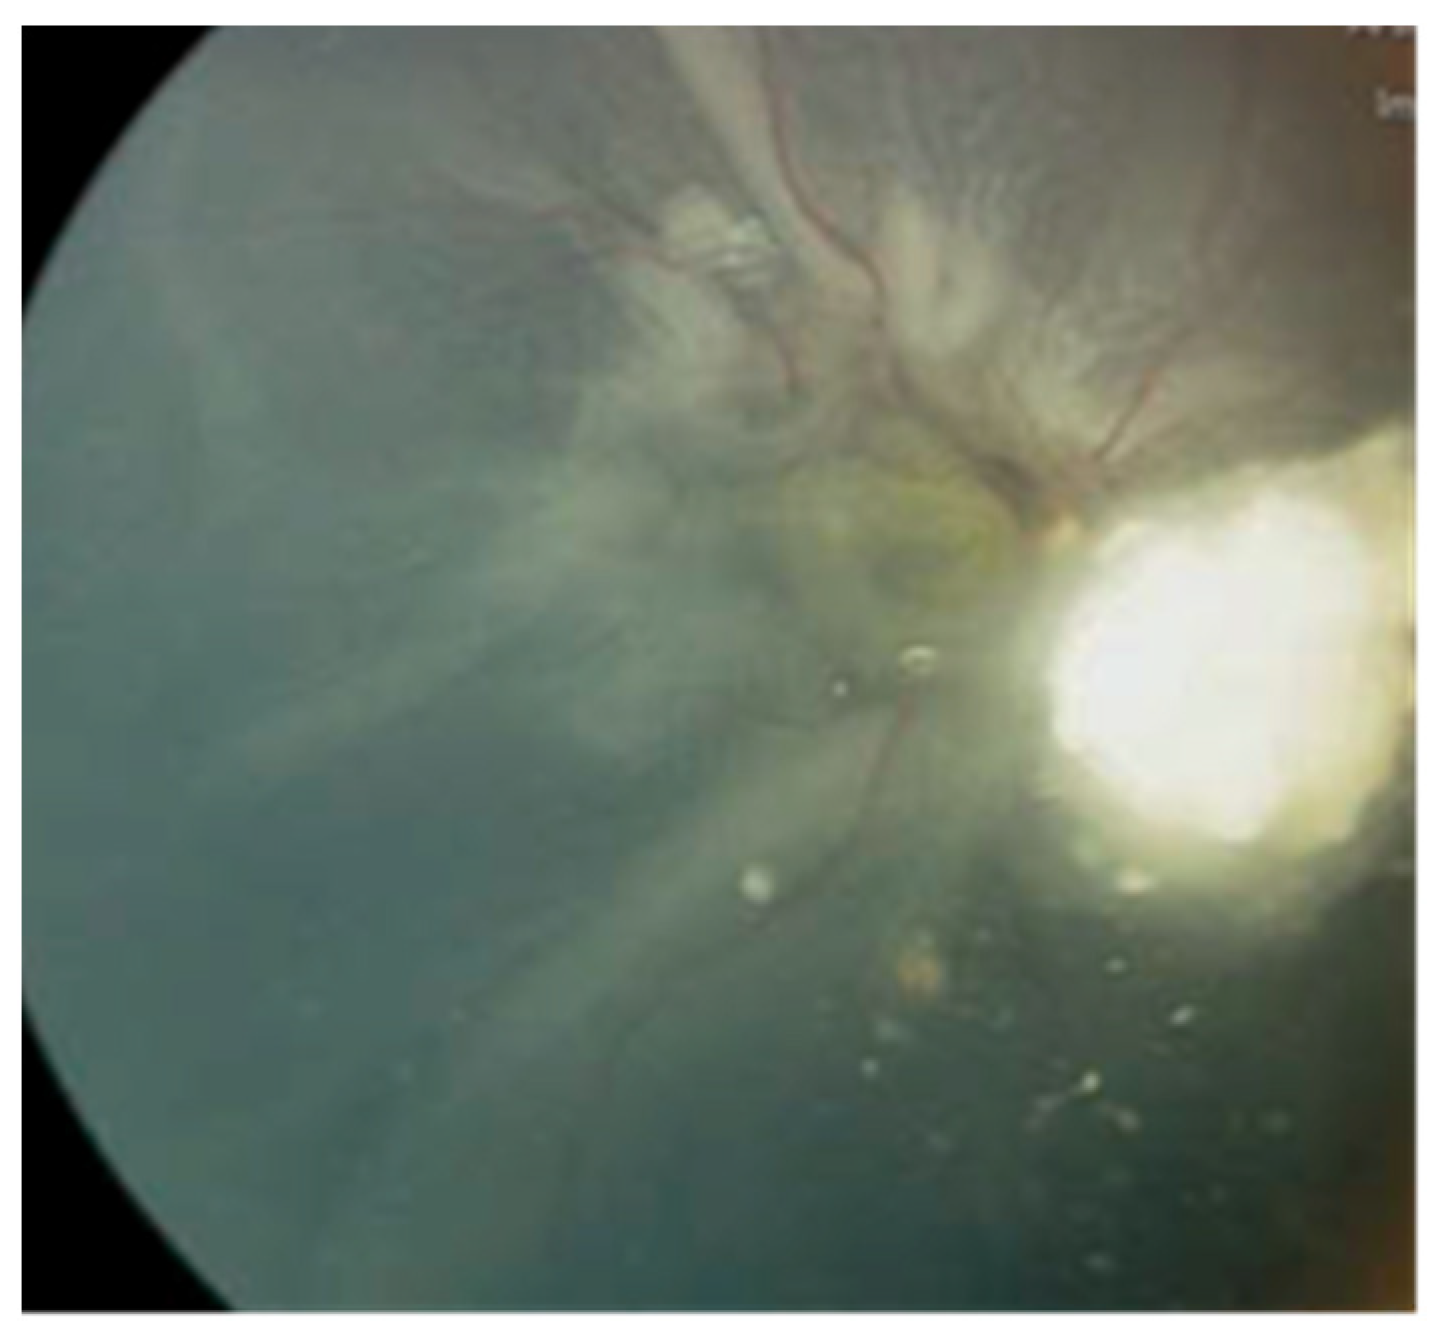

Case #3: A 2-year-old male, diagnosed with bilateral Rb, had already undergone enucleation for the left eye in a different country. Before being referred to our center, he received six cycles of systemic chemotherapy to manage the active tumors in the right eye. Upon the first assessment at our center, the right eye exhibited active Rb, subtotal RRD, and a tractional component (

Figure 2).

An effort was made to address the retinal detachment using a conventional approach involving scleral buckling and retinopexy without fluid drainage. While there was a minor improvement in the retinal detachment after the surgical procedure, the tumor displayed resistance to chemotherapy and continued to enlarge. The retina failed to reattach over a three-month postoperative follow-up period, and the tumor persisted in its growth. Due to the poor prognosis for vision and the heightened risk of metastasis, the decision was ultimately made to proceed with enucleation of the right eye.